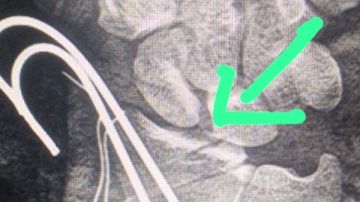

وأوضح الدكتور أحمد البيلي، وكيل المديرية للطب العلاجي، أن الفريق الطبي تعامل بسرعة واحترافية عالية مع الحالة، وتم نقل المريض فورًا إلى غرفة العمليات، حيث جرت الجراحة بدقة متناهية، باستخدام الميكروسكوب الجراحي لإعادة توصيل الأوتار القابضة والباسطة، وربط الشرايين لإعادة التروية الدموية، وإصلاح الأعصاب الطرفية باستخدام خيوط ميكروسكوبية فائقة الدقة.

وأشار إلى أن المريض خرج من العملية بحالة مستقرة، مع استعادة فورية للتروية الدموية وتحسن تدريجي في الإحساس والحركة، وتم إدخاله في برنامج تأهيلي متكامل بإشراف فريق العلاج الطبيعي بالمستشفى.